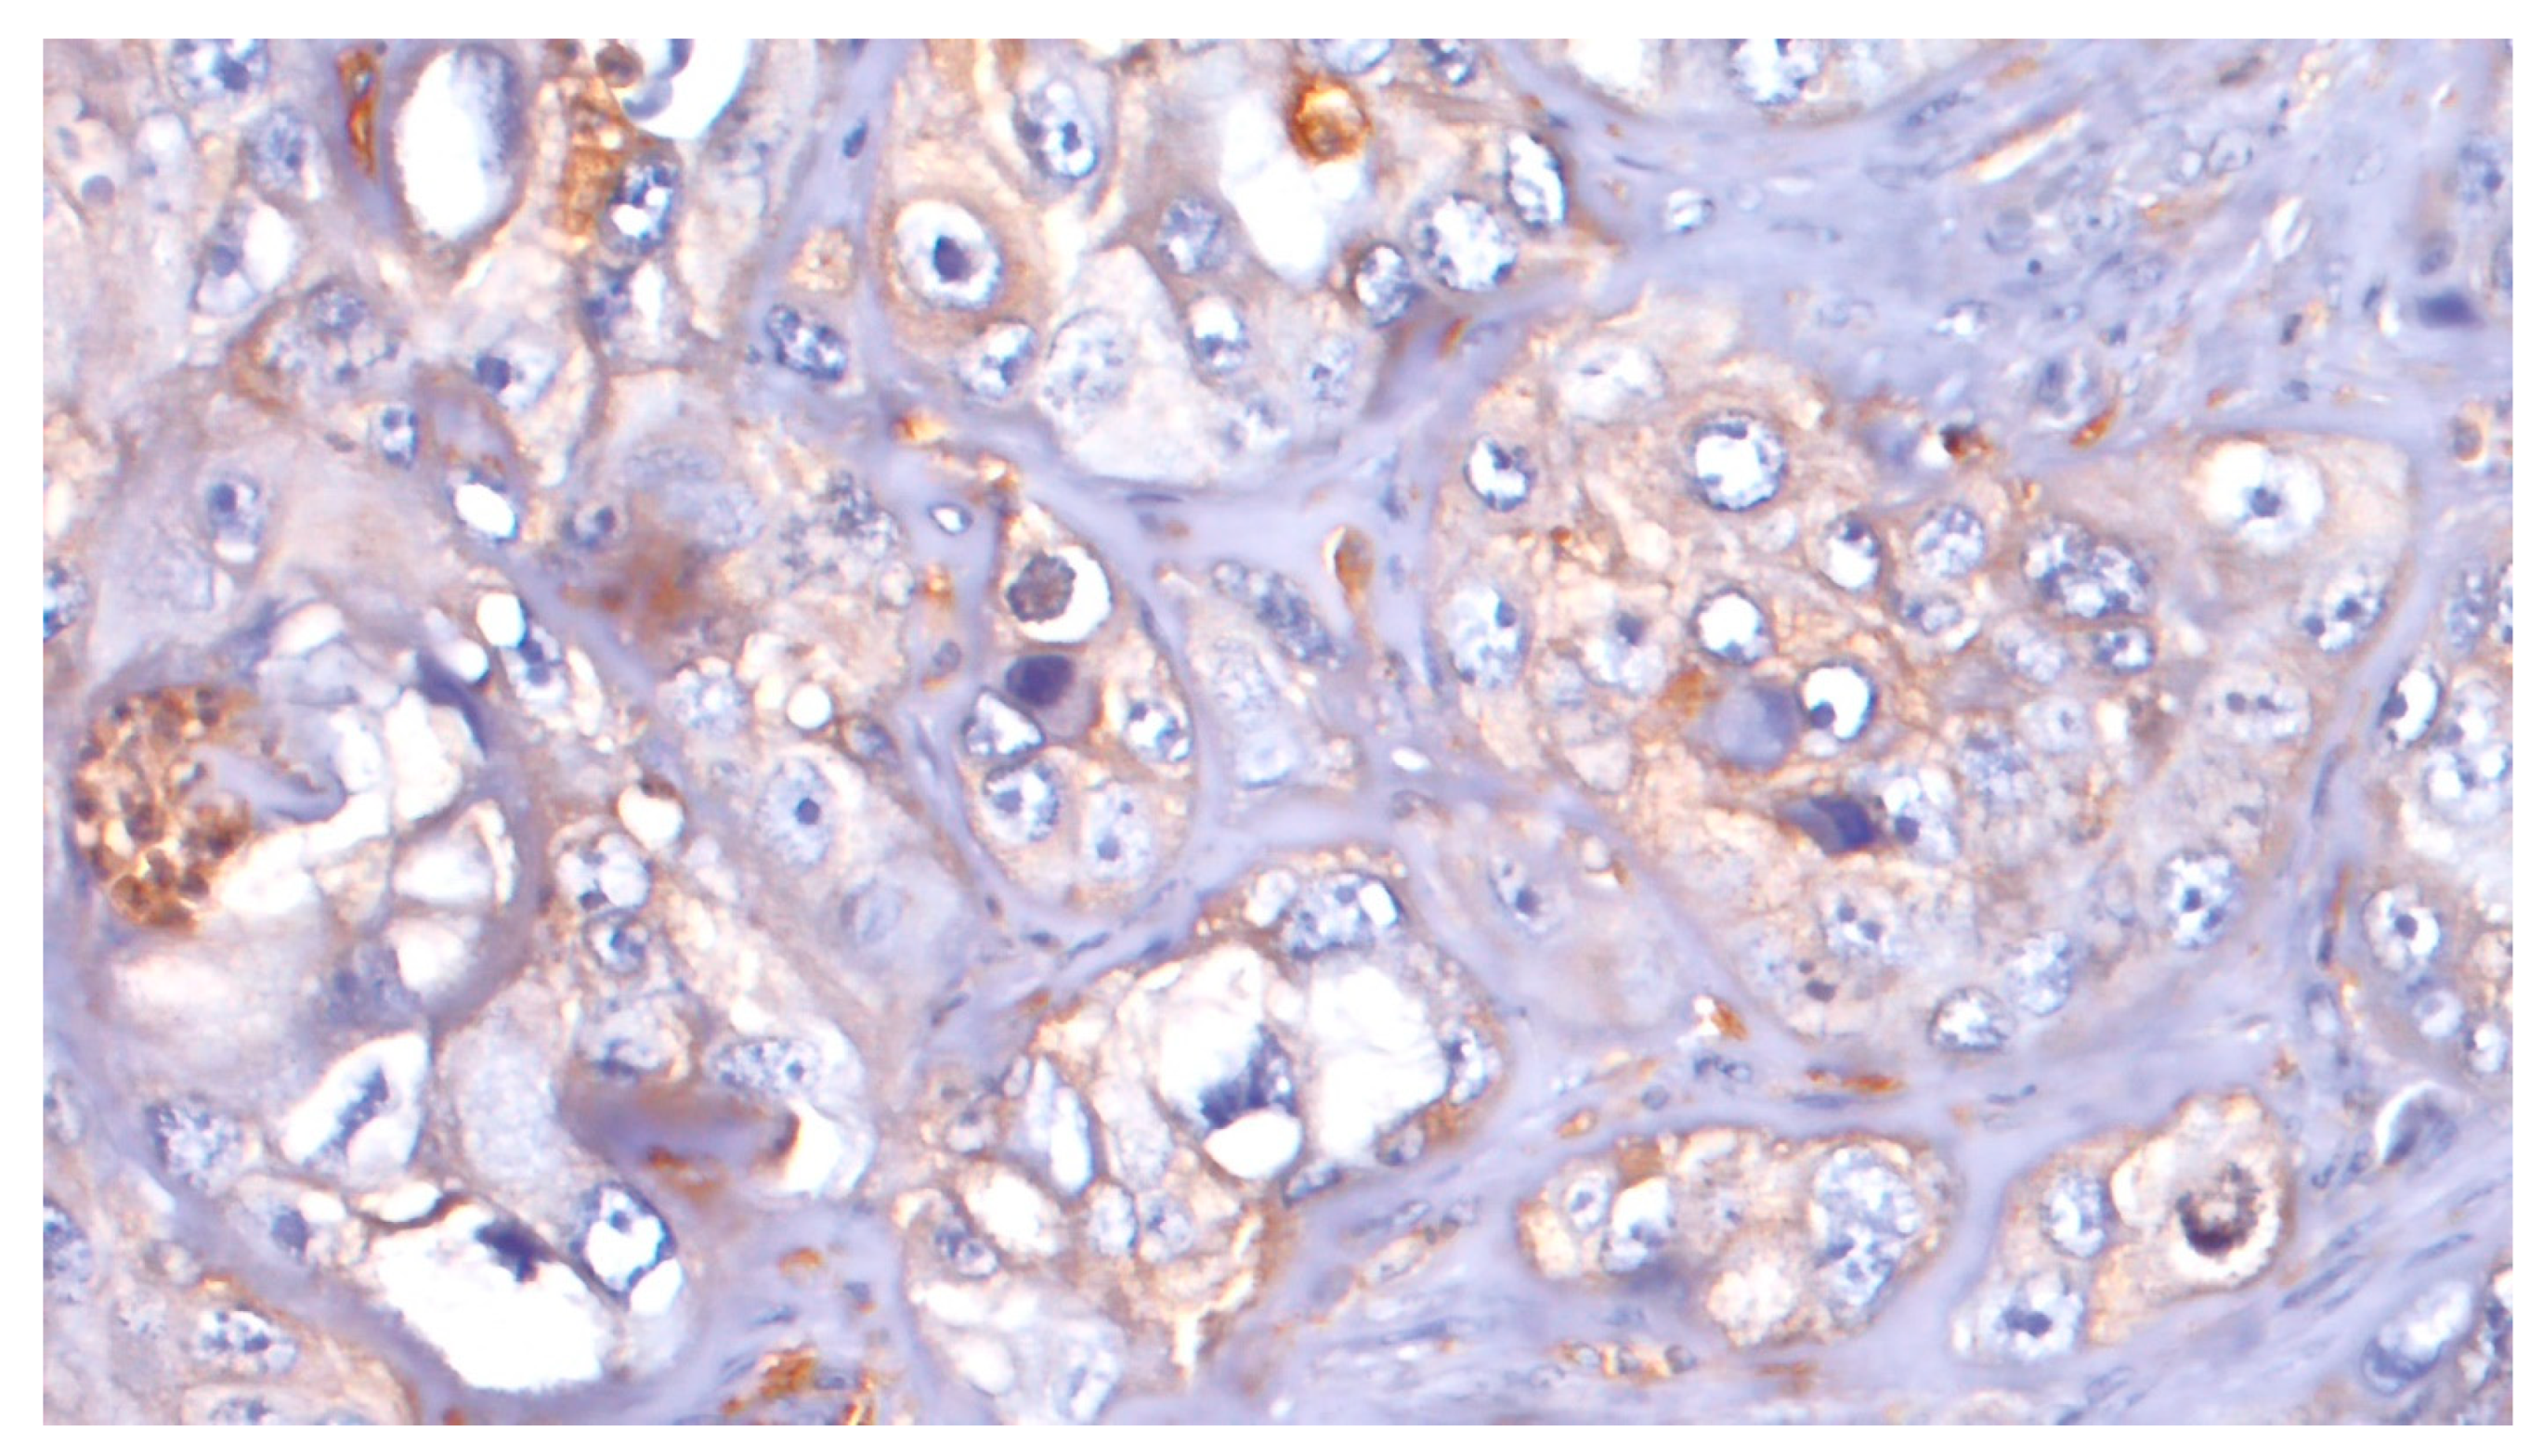

4.2. CD44 Expression

4.3. PDL1 Expression

4.4. ATG7 Expression